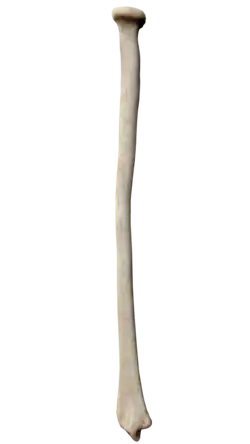

The radius or radial bone (pl.: radii or radiuses) is one of the two large bones of the forearm, the other being the ulna. It extends from the lateral side of the elbow to the thumb side of the wrist and runs parallel to the ulna. The ulna is longer than the radius, but the radius is thicker. The radius is a long bone, prism-shaped and slightly curved longitudinally.

The radius has a body and two extremities. The upper extremity of the radius consists of a somewhat cylindrical head articulating with the ulna and the humerus, a neck, and a radial tuberosity.[1] The body of the radius is self-explanatory, and the lower extremity of the radius is roughly quadrilateral in shape, with articular surfaces for the ulna, scaphoid and lunate bones. The distal end of the radius forms two palpable points, radially the styloid process and Lister's tubercle on the ulnar side. Along with the proximal and distal radioulnar articulations, an interosseous membrane originates medially along the length of the body of the radius to attach the radius to the ulna.[2]

The body of the radius (or shaft of radius) is prismoid in form, narrower above than below, and slightly curved, so as to be convex lateralward. It presents three borders and three surfaces.

The upper extremity of the radius (or proximal extremity) presents a head, neck, and tuberosity.